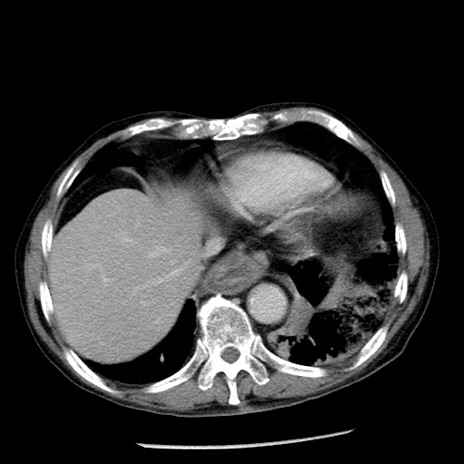

症例26(横断像)

【症例】80歳代男性

【主訴】嘔吐

【現病歴】昨晩2回嘔吐あり、今朝になっても嘔吐あり。来院。

【既往歴】胃潰瘍

【身体所見】意識清明、BT 37.6℃、BP 166/95mmHg、HR 100bpm、SpO2 97%、腹部:平坦・軟、腸蠕動音聴取良好、圧痛なし。

【データ】WBC 21900、CRP 1.46